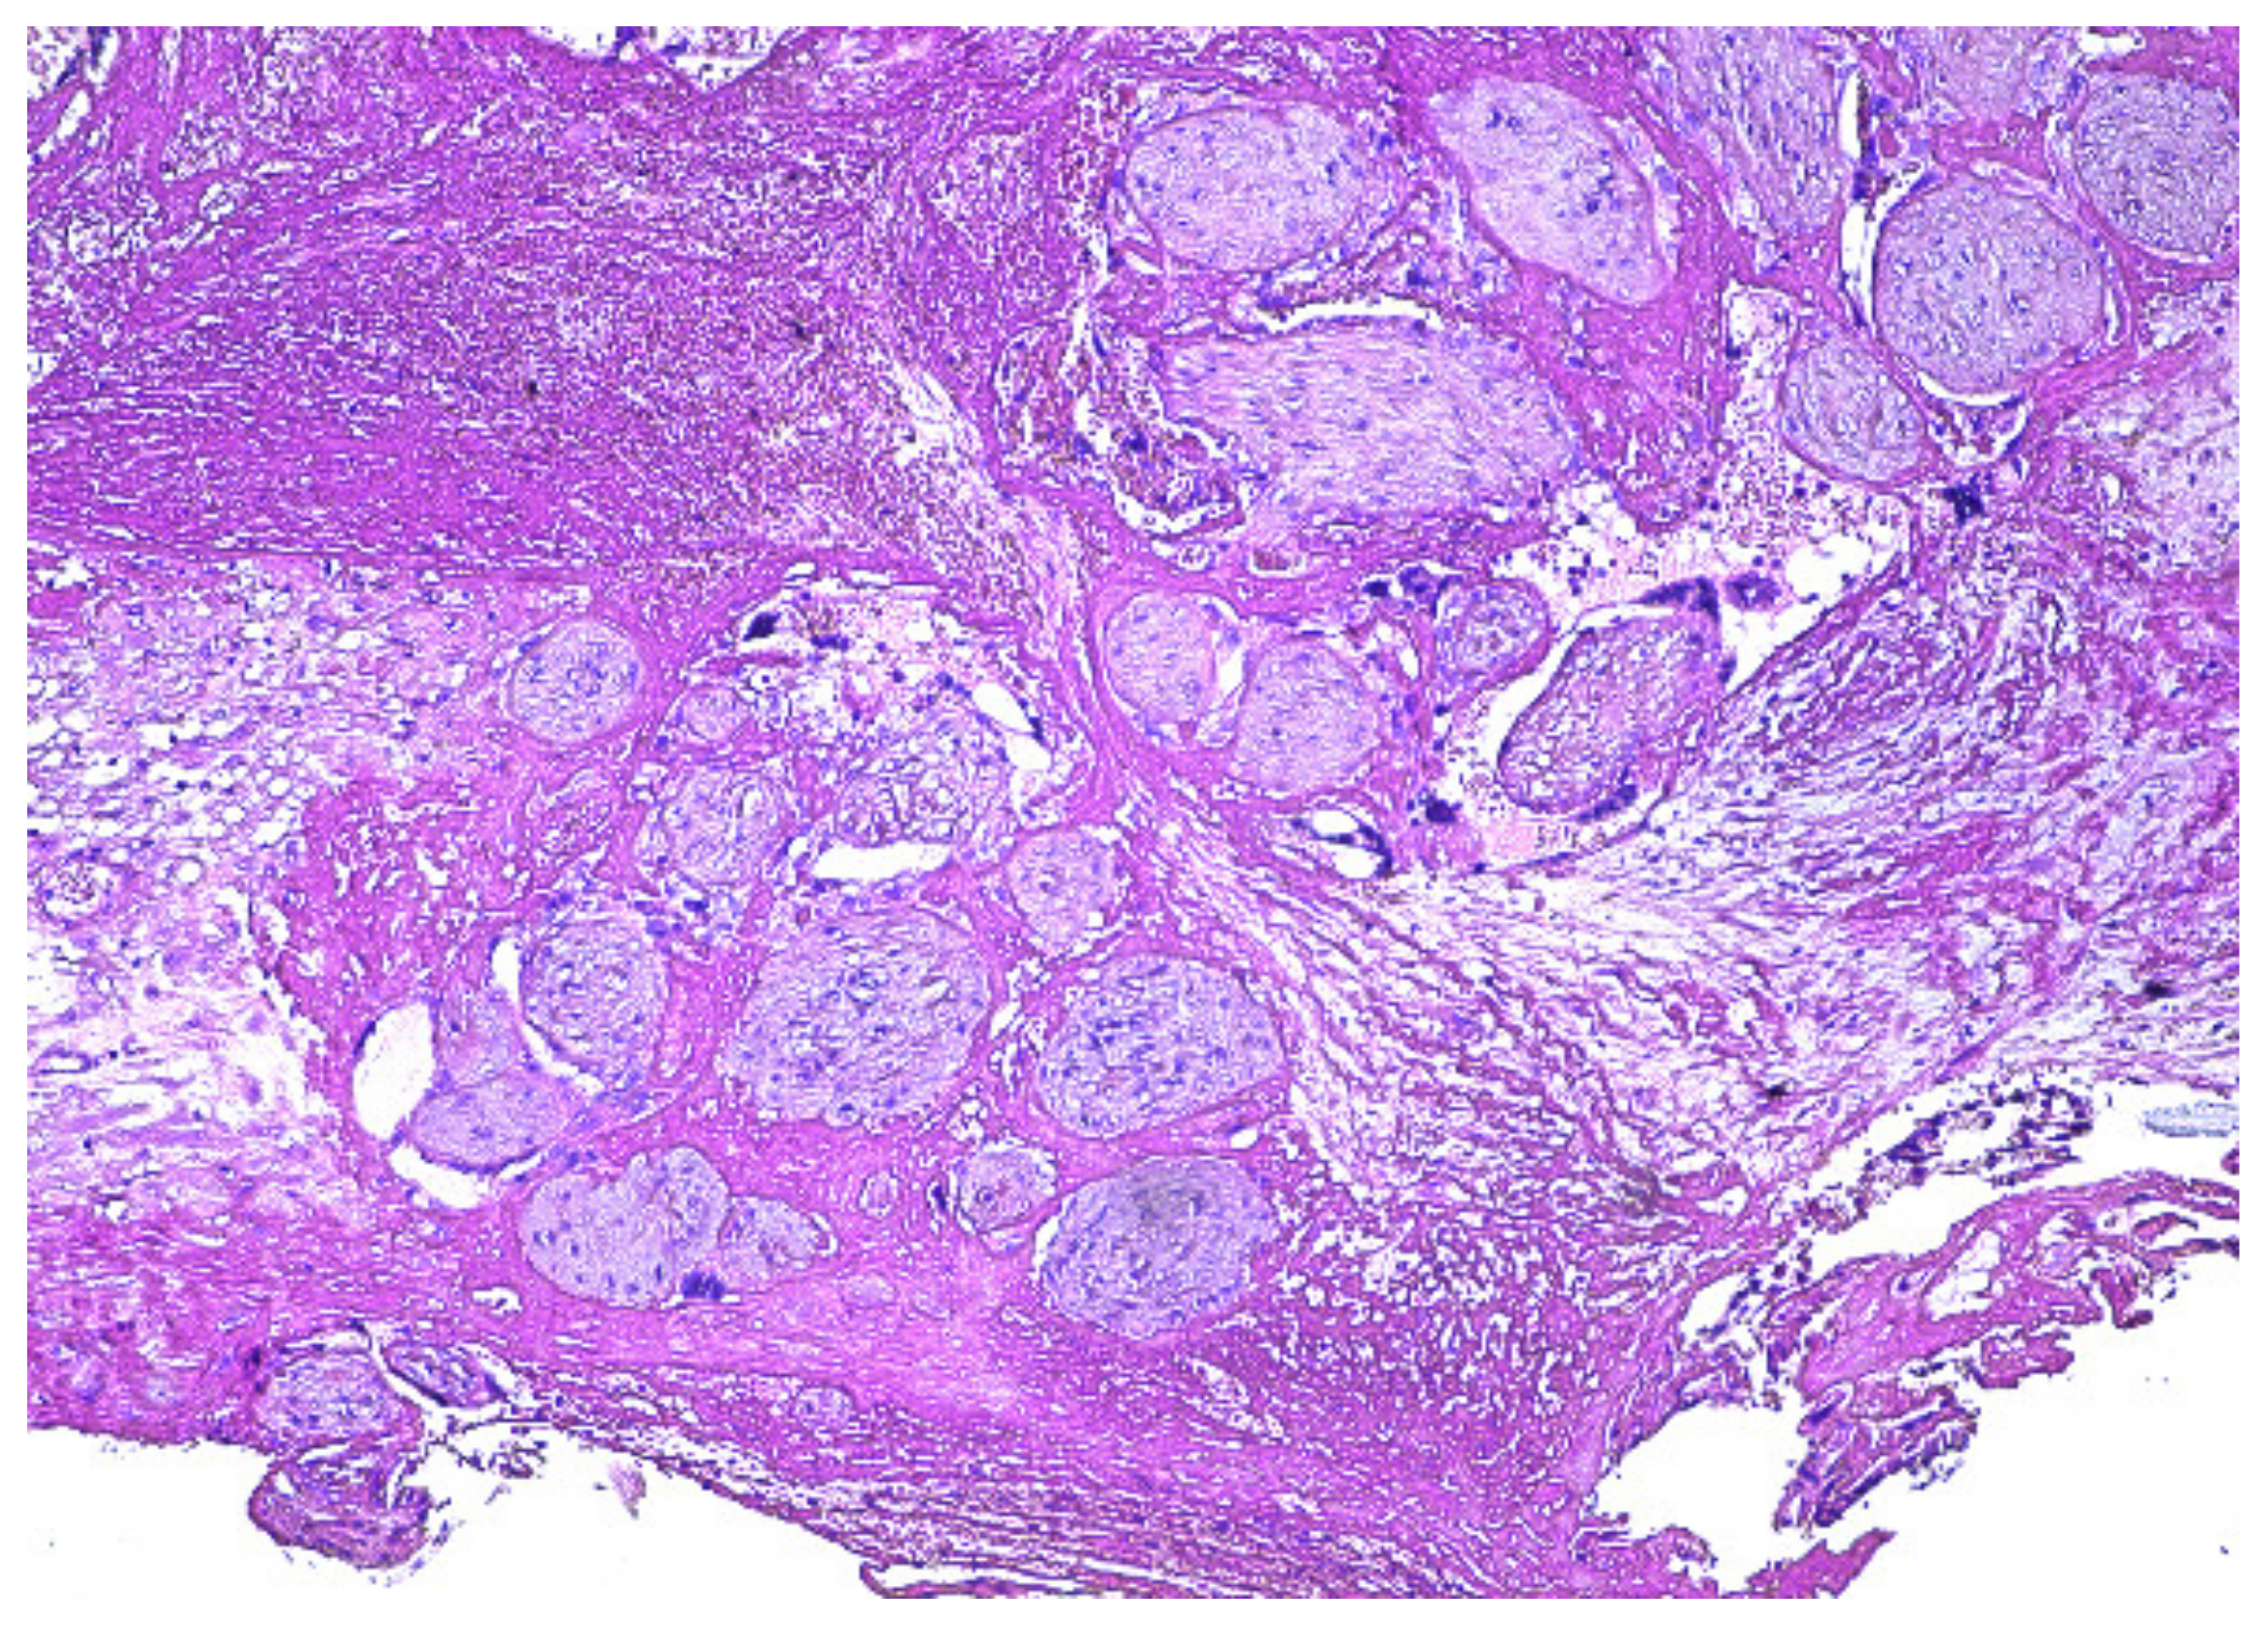

2. Case Presentation